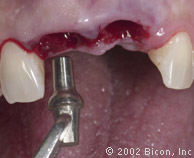

Формирование ложа имплантанта

Paralelling Pins

Pilot drill

Osteotomy

Curette